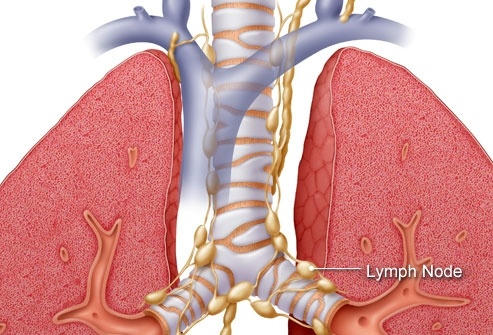

Các giai đoạn ung thư phổi

Mỗi loại ung thư phổi có cách xâm lấn khác nhau trong cơ thể. Như ung thư phổi tế bào nhỏ được chia thành hai giai đoạn: Giai đoạn giới hạn có nghĩa là ung thư được giới hạn trong một phổi và các hạch bạch huyết có thể ở gần vị trí khối u. Giai đoạn ung thư lan rộng có nghĩa là ung thư đã lan rộng khắp phổi hoặc ra các bộ phận khác. Ung thư phổi không phải tế bào nhỏ được chia thành từ 1 đến 4 giai đoạn, tùy thuộc vào việc khối u lan rộng đến đâu.